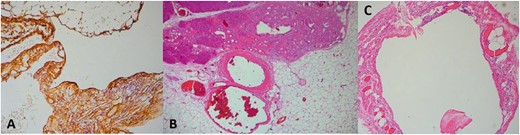

Due to the increased size and the long-lasting pressure symptoms of the cystic lesion, surgical exploration was decided at the multi-disciplinary team (MDT) meeting with the patient’s approval. The patient underwent exploratory laparotomy through a midline incision. The cystic mass was found to originate from the tail of the pancreas, adherent to the upper pole of the spleen. The mass was carefully mobilized from the adjacent structures and the resection was completed by en-bloc distal pancreatectomy with splenectomy and cholecystectomy (Fig. 2). The patient had an uncomplicated postoperative course and was discharged on post-operative day 5. Gross examination revealed a 13 × 11 × 7 cm well-described cystic tumour filled with yellowish fluid. On histopathological evaluation, the lesion consisted of anastomosing lymphatic spaces lined by a single layer of endothelial cells. The endothelial cells were positive for CD34, CD31, and D2-40 and negative for pankeratin (Fig. 3). The diagnosis of lymphangioma was made. There was no evidence of malignancy. Splenic and pancreatic tissues were found to be normal. Gallbladder specimen presented signs of chronic lymphocytic inflammation indicative for chronic calculus cholecystitis. MDT decision was follow-up. The patient is asymptomatic with no evidence of recurrence in 6 months.

Upon pathology examination pancreatic cystic lymphangiomas are multilobulated and on cut section the smaller cysts interconnect representing multiple dilated lymphatic channels. Histologically, there are three types of lymphangiomas—cystic, capillary, and cavernous—but only the cystic and cavernous types have been reported in the pancreas. [8] Histologically, dilated lymphatic spaces along with attenuated endothelial cells are observed. [4] Immunohistochemically, lymphangiomas are positive for VIII-R antigen, CD31, and D2-40 and negative for CD34 [8] which however may occasionally be positive [12] as it presented in our case. They are negative for epithelial markers or periodic acid–Schiff stain [8].